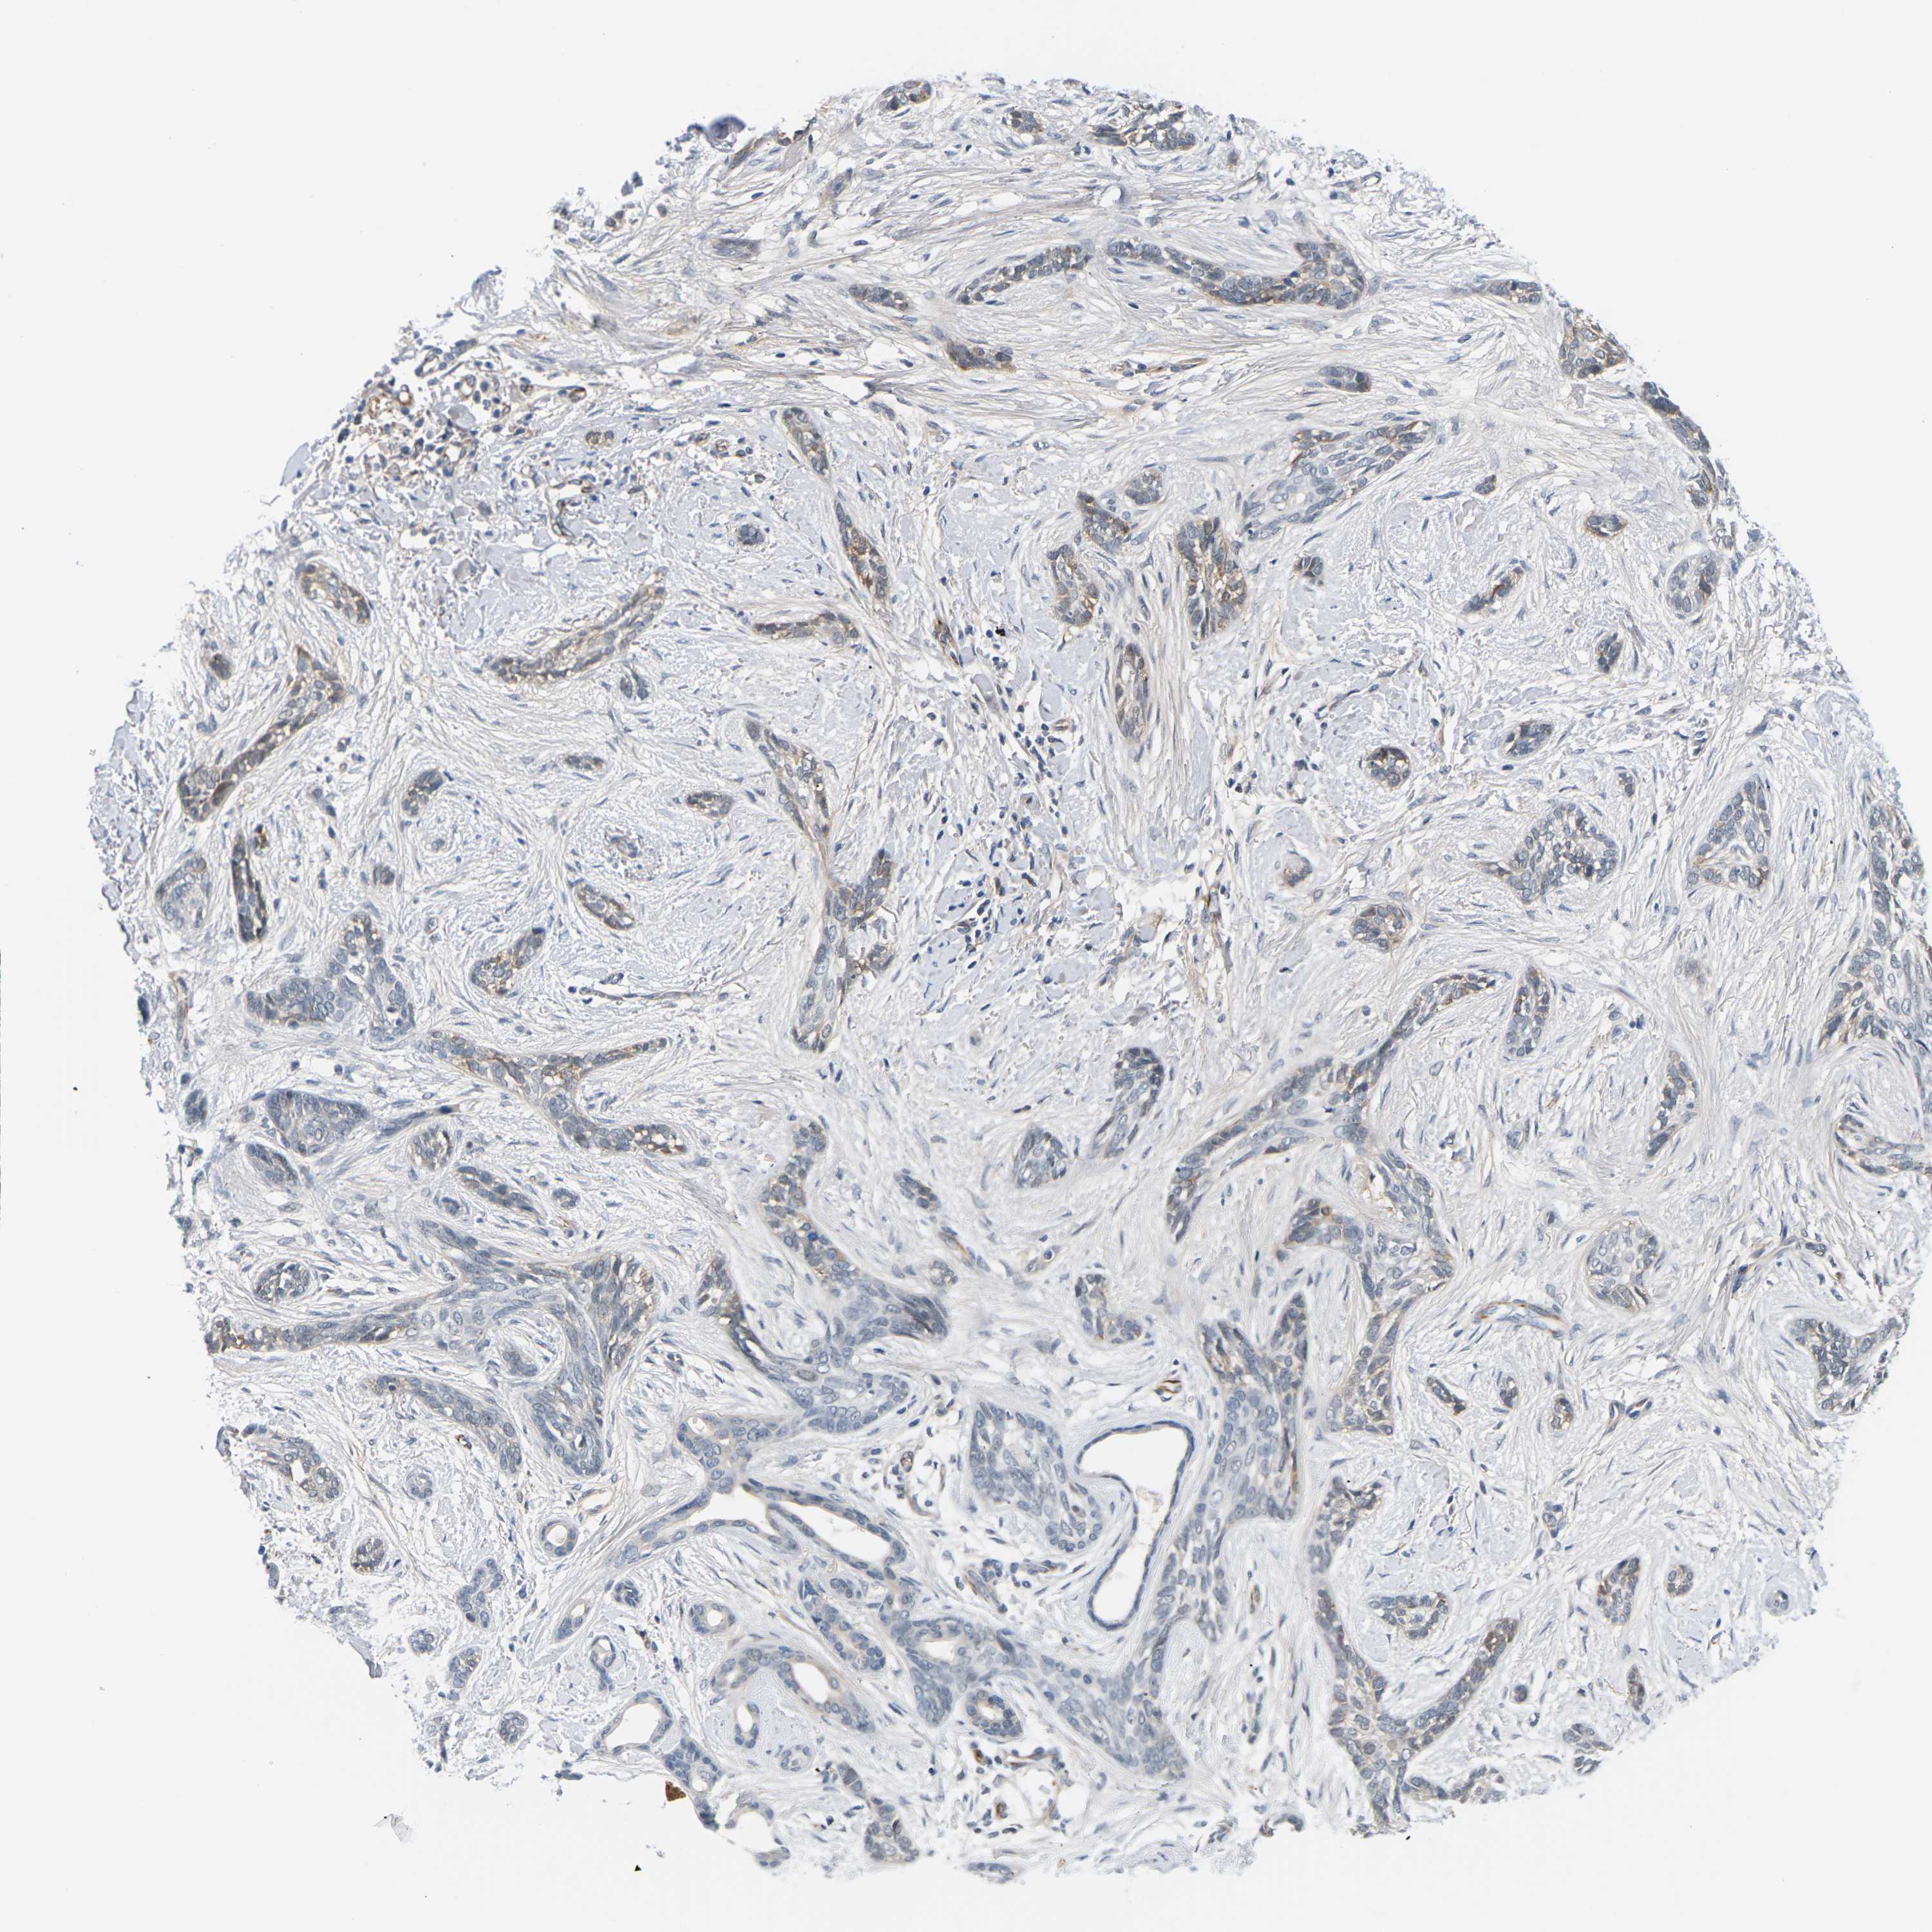

SKIN CANCER - Protein expressioni

A mouse-over function shows sample information and annotation data. Click on an image to view it in a full screen mode. Samples can be filtered based on level of antibody staining by selecting one or several of the following categories: high, medium, low and not detected. The assay and annotation is described here.

Antibody stainingi

Antibody staining in the annotated cell types in the current human tissue is reported as not detected, low, medium, or high, based on conventional immunohistochemistry profiling in selected tissues. This score is based on the combination of the staining intensity and fraction of stained cells.

Each image is clickable and will lead to virtual microscopy that enables deeper exploration of all samples and also displays staining intensity scores, fraction scores and subcellular localization as well as patient and tissue information for each sample.

Antibody CAB037336

Basal cell carcinoma

Adnexal tumor, benign